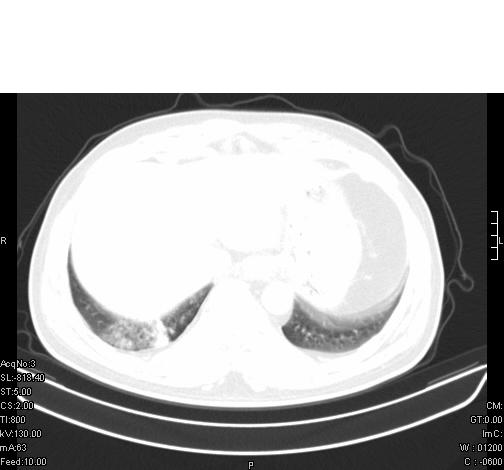

标题: CT6685:右肺阻塞性炎症,增强CT。

前几天,发了患者的平扫片,患者抗炎一周后增强扫描。右中叶病灶吸收明显,但下叶病灶未见明显吸收。右肺门可见结节影,看来凶多吉少

右肺下叶支气管管腔狭窄,管壁增厚,右下肺见斑片状高密度影,考虑右侧肺门中心肺癌伴阻塞性肺炎

右肺下叶散在的斑片状致密影,下叶支气管变窄。考虑:右肺慢性炎症。

右肺下叶支气管壁不规则增厚,右肺下叶有斑片状影分布。考虑右肺中央型肺癌伴右肺下叶阻塞性改变。建议支纤镜检查。平扫比增强较好显示了病变情况。

既然抗炎治疗有效,可继续治疗;右肺下叶支气管管腔狭窄,管壁增厚,右下肺见斑片状高密度影,右侧主支气管后见结节影(淋巴结?),肺癌不能排出。